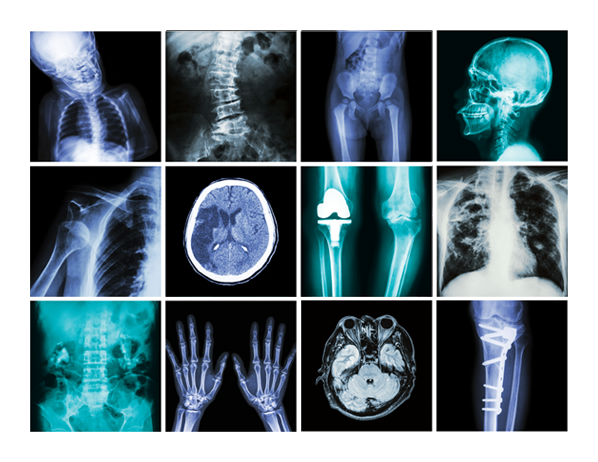

- Radiology

Radiology

The department of Radiology has got all latest and International class machines to diagnose diseases and to take prompt actions.

X-Ray- Panacea Hospital has got latest X-ray machines of AllengerT Which help penetrating ionizing radiation to take picture of dense tissues.

CT Scan- Hospitals consists computed tomography (CT) scans of GET company which allows to see inside body with the co-ordination of computer to produce pictures of required object.

Ultrasound - Panacea Hospital nests very latest ultrasound machines to see internal body structure such as tendons, muscles, joints, blood vessels and internal organs.